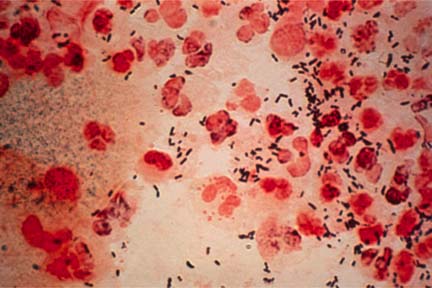

Gonoreea

Gonoreea este o infectie bacteriana grava. Barbatii pot avea arsuri cand urineaza

si o secretie din penis. Femeile pot avea secretii si iritatii vaginale, sau

dureri cand urineaza. Majoritatea femeilor si unii barbati nu vor avea semne

timpurii ale bolii.

Diagnosticarea poate fi facuta prin examinarea secretiilor la microscop.